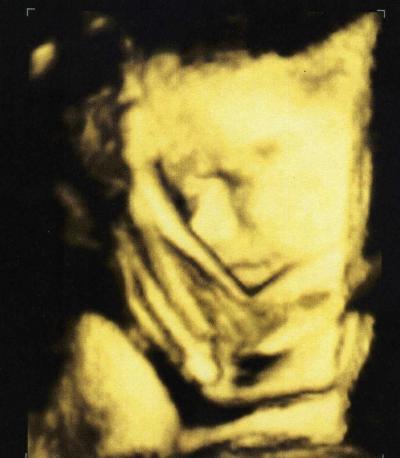

Hallo Mädels, Daumen drücken hat geholfen...mit meinen beiden ist alles suuper...:-) Keinerlei Rhythmusstörungen zu finden... beide sind auch super gewachsen und wiegen schon über 2000g... Habe noch zwei wunderschöne Bilder dazu bekommen...das erste ist von der kleinen Maus, das zweite vom Brüderchen...zum verlieben..